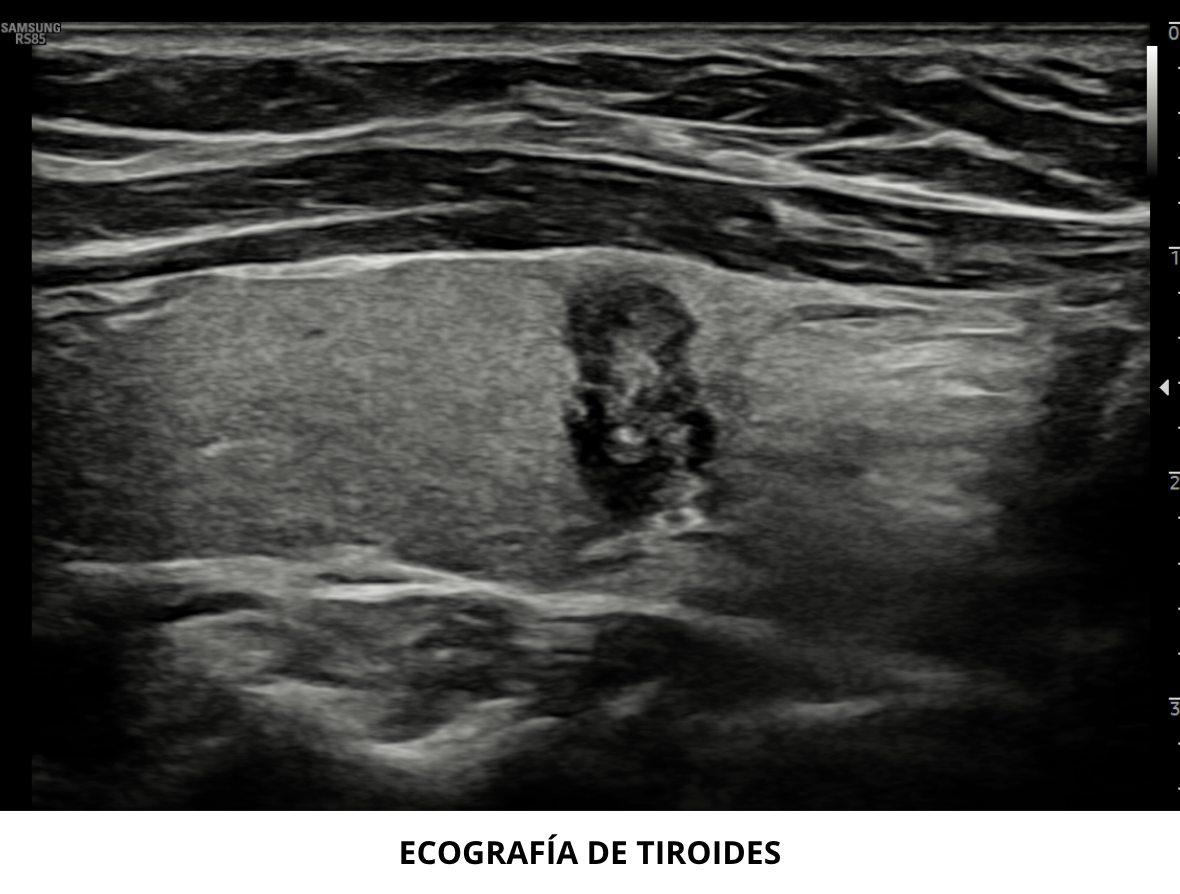

• Ecografía de tiroides de alta resolución

Ecografía de Tiroides